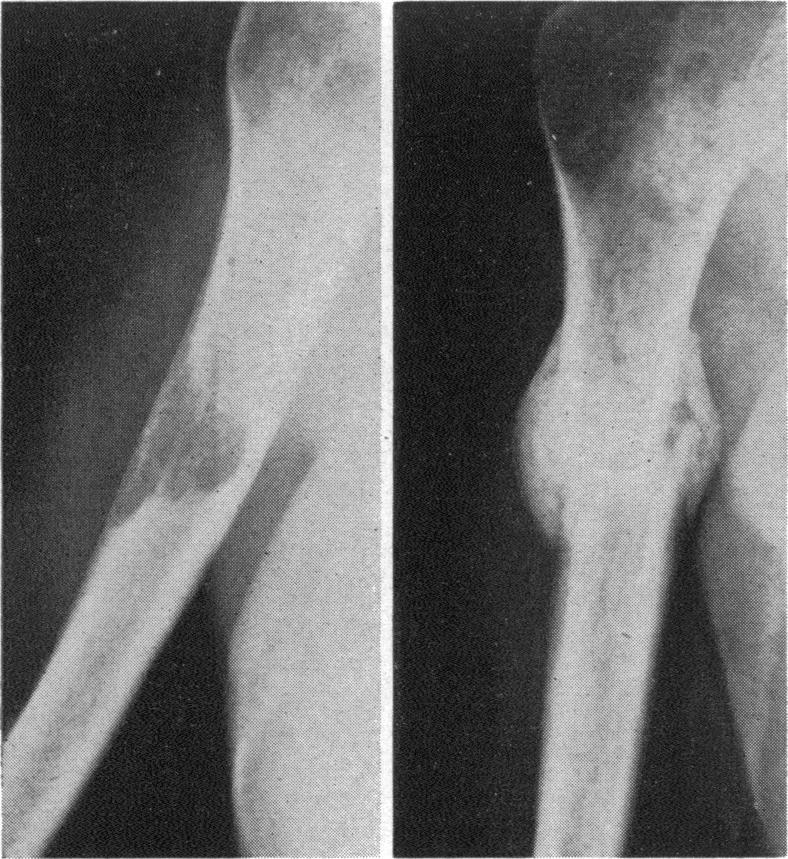

Breast cancer; a new approach to therapy.

Br Med J. 1959 May 23;1(5133):1315-20. doi: 10.1136/bmj.1.5133.1315.